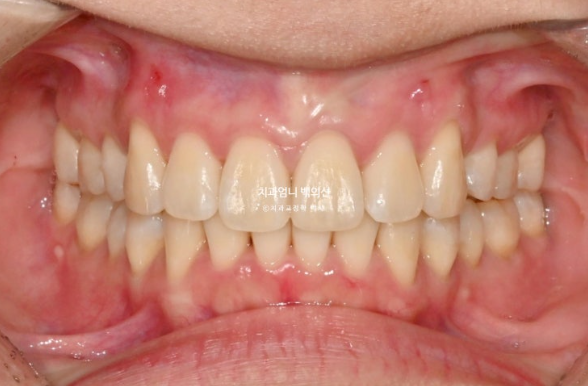

정면을 보시면 윗니가 아랫니를 많이 덮고 있습니다.

아랫니가 거의 보이지 않습니다.

이런 부정교합을 과개교합 이라고 합니다.

윗니도 많이 뻗쳐 있습니다.

배열도 좋지 않아서 발치교정 권유드렸습니다.

개선된 과개교합과 일치된 중심선

앞니 뻗침도 많이 좋아졌습니다.